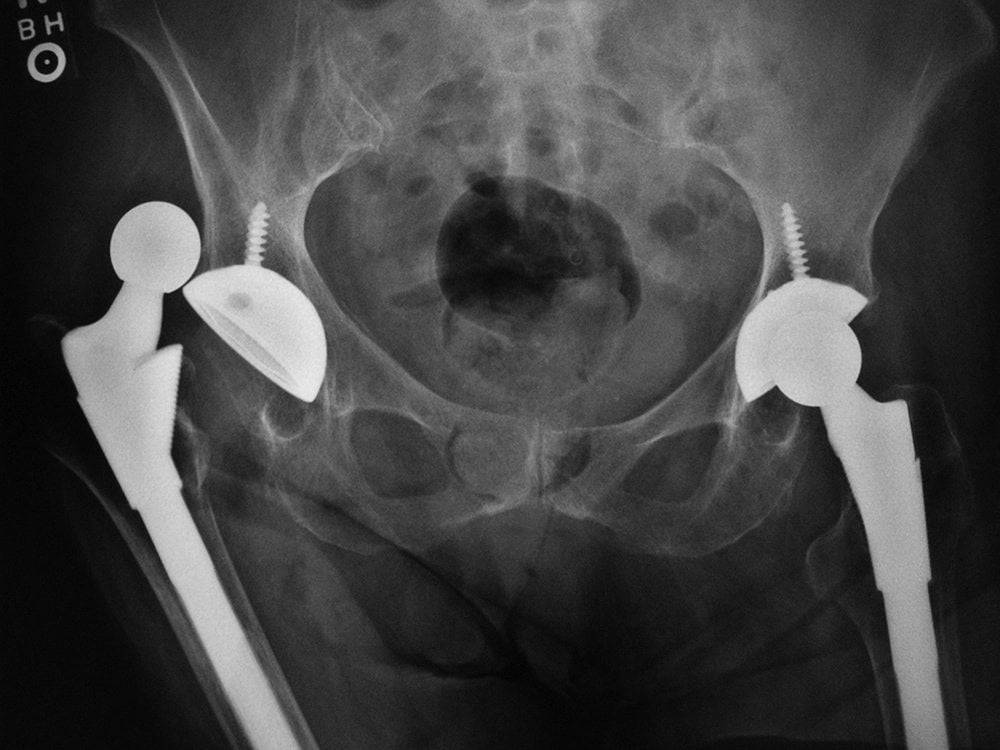

После тотальной операции по замене сустава.

После одномыщелковой замены сустава.